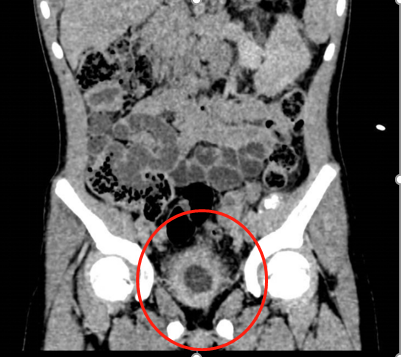

正因?yàn)楹⒆訉?duì)治療的勇敢配合,加上外四科全體醫(yī)護(hù)人員的專業(yè)醫(yī)治與細(xì)心照顧,接下來(lái)的第二次“腹腔鏡下右腎切除術(shù)”與第三次“回腸膀胱擴(kuò)大術(shù)”也都順利完成。CT掃描下,妞妞術(shù)后的膀胱是一個(gè)有特別含義的“愛(ài)心”形狀;膀胱容量也從最初的15ml—20ml擴(kuò)大至250ml—300ml左右,目前她已和常人無(wú)異,平均4小時(shí)左右才需進(jìn)行一次排尿。

膀胱擴(kuò)大術(shù)后的“愛(ài)心”形狀